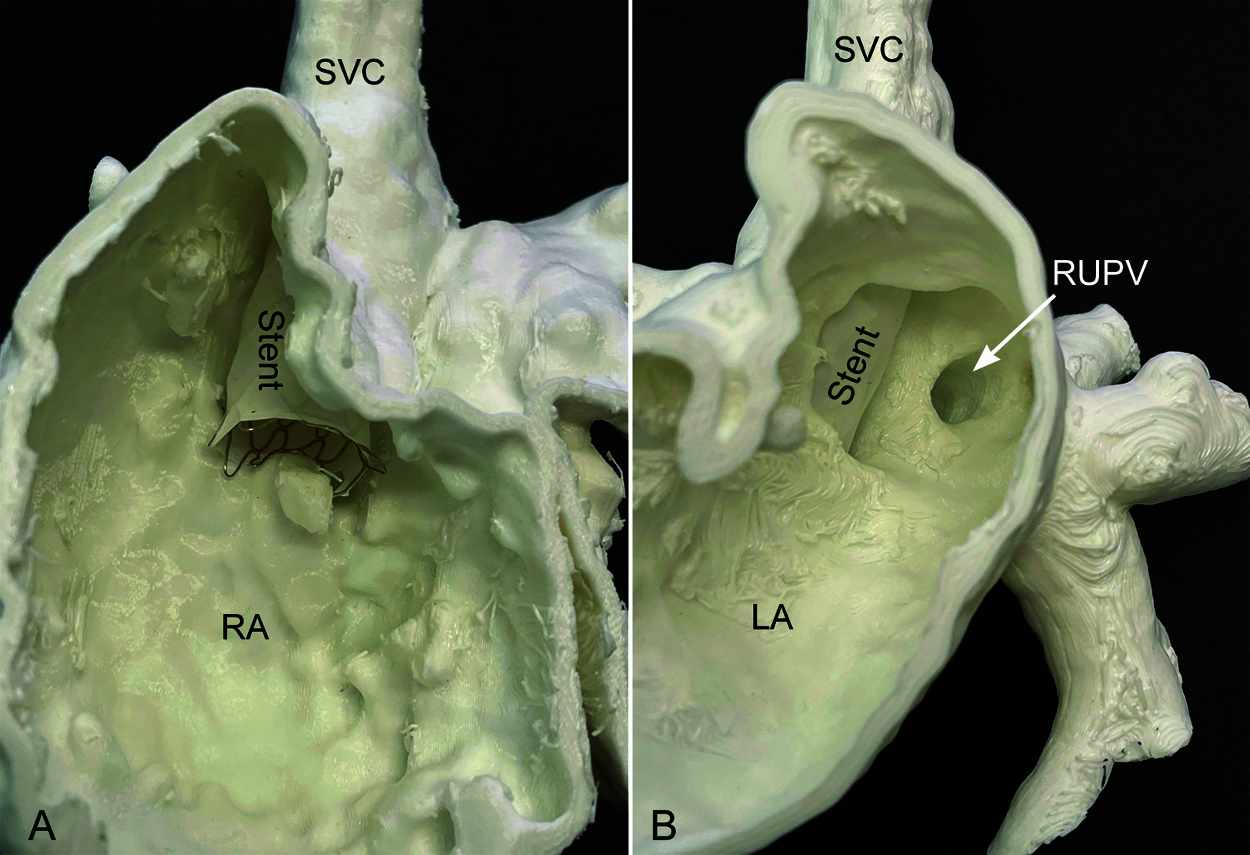

While 3D echocardiography is helpful in assessment of the intracardiac anatomy, both MRI and CT are excellent tools for realistic 3D visualization of the normal and anomalous pulmonary veins [44–48]. MRI is the most comprehensive imaging modality that provides not only precise 3D anatomical information but also accurate hemodynamic data including the amounts of shunt through the defect and anomalous pulmonary vein(s) and the ventricular volumes and function [44–47]. Both MRI and CT angiograms can be used for 3D modeling and printing for feasibility of catheter-based closure of the defect or surgical guidance and simulation (Fig. 16) [49–53].

Figure 16: 3D printed model of superior sinus venosus defect. Feasibility of the placement of a covered stent is tested on the model. The inside of the right atrium in A shows that the stent is well positioned from the lower superior vena cava (SVC) to the right atrium (RA) across the defect. The inside of the left atrium in B shows that the orifice of the right upper pulmonary vein (RUPV) is left behind the stent so that it drains to the left atrium (LA)

Since its introduction in 2013 by Abdullah et al. and in 2014 by Garg et al, transcatheter approach using a covered stent has increasingly been adapted [53,70–72]. A large clinical series showed a suitability of transcatheter correction in >75% of patients with superior sinus venosus defect [53]. Unsuitability of the procedure included the connection of the anomalous pulmonary vein(s) to the superior vena cava well above the right atrial junction or along the anterior wall, potential pulmonary venous compression with stenting and large defects. Catheter treatment of the inferior sinus venosus defects has been regarded unfeasible with only a few cases reported in the literature [73,74].